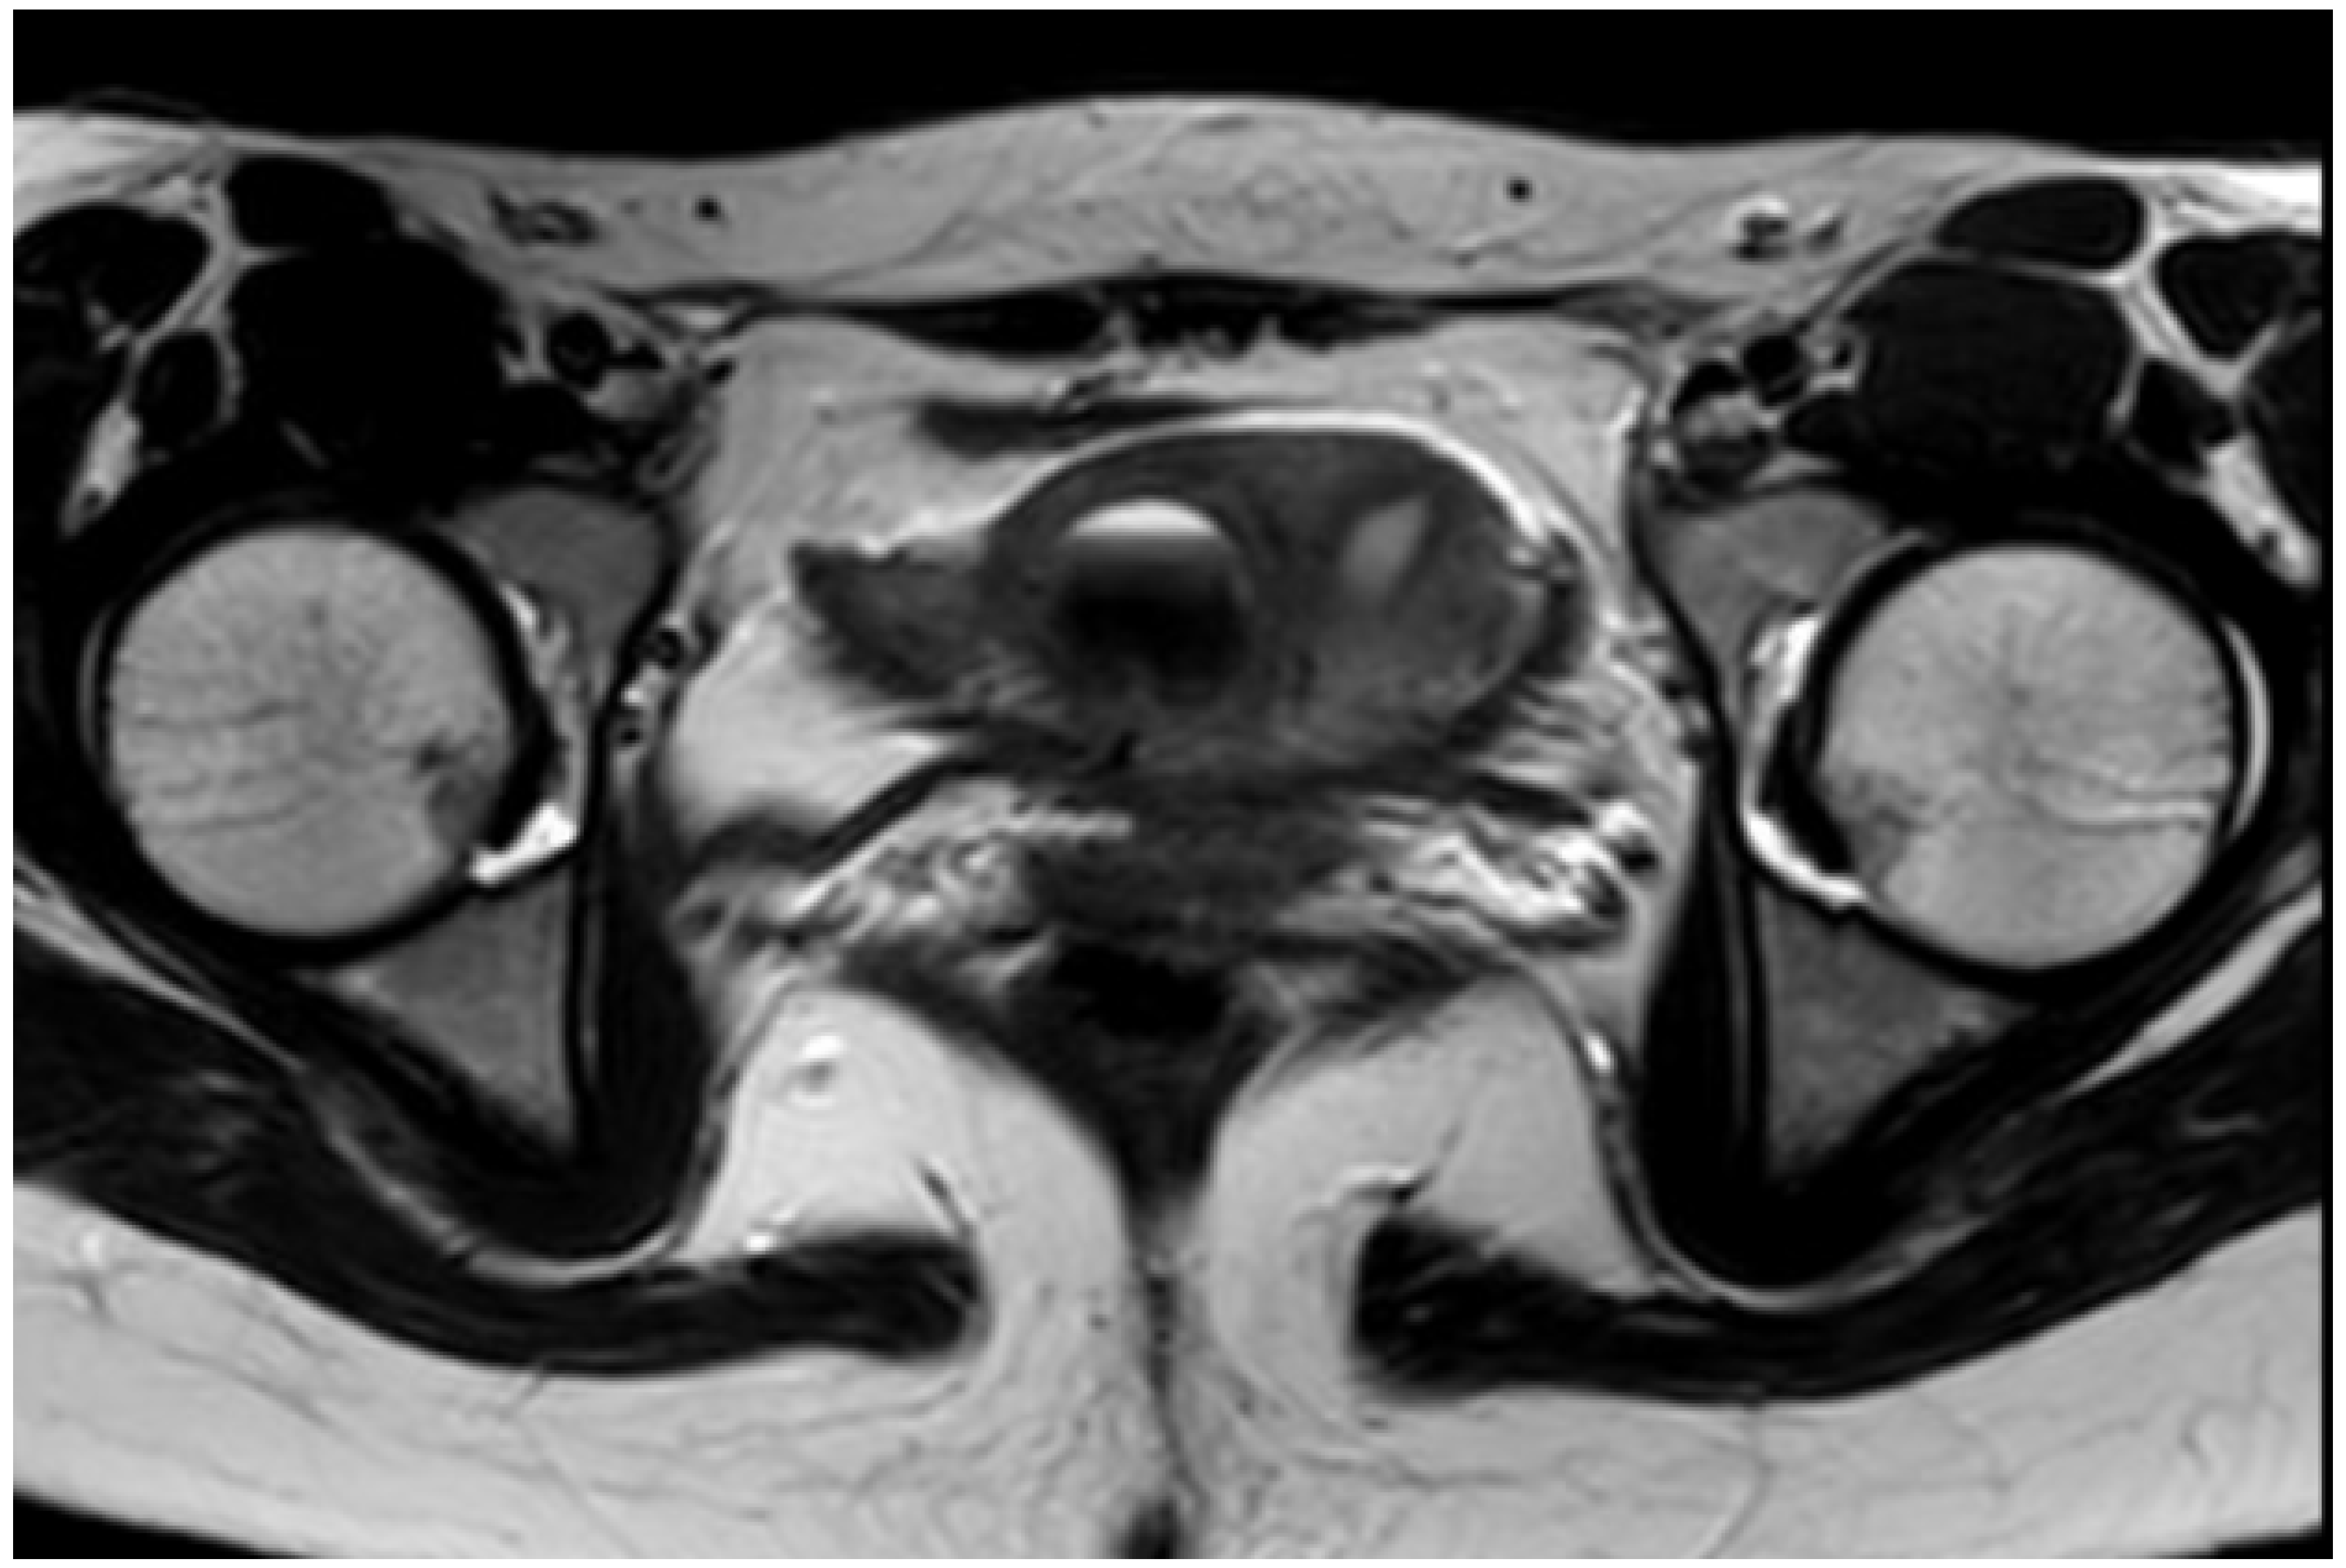

Results and Discussion: A healthy 9 year old girl was referred to our outpatient clinic of Pediatric Gynecology because of vaginal bleeding since two months, without trauma and accompanied by mild abdominal discomfort. She suffered from daily vaginal bleeding, varying from spotting to small blood clots. No vaginal discharge, pruritus, fever or constipation. She did not use medication. Physical examination showed a 1.29 m height girl, weighing 28 kg with Tanner stage 1. Genital examination showed normal prepubertal external genitalia without skin lesions or vaginal discharge. A vulvovaginal sample for bacterial culture was normal. Abdominal ultrasound showed an enlarged uterus with a 2.2 cm hyperechogenic intracavitary mass without blood flow (Figure 1) and normal ovaries. It was concluded to be hematometra. MRI confirmed normal development of internal genitals and hematometra. Blood results were (repeatedly): Hb 7.0 mmol/L; FSH 0.7 IU/L; LH < 0.1 IU/L; estradiol < 20 pml/L. Normal values of infection markers, tumor markers, thyroid function and testosterone. Hysteroscopy was performed under general anesthesia and showed a round, pale pedunculated intracavitary structure. Biopsies showed a thrombus, without signs of malignancy. In a following hysteroscopy the structure was completely removed without significant blood loss. The pathology report showed a benign capillary-venous malformation.

Figure 1.

Abdominal ultrasound.